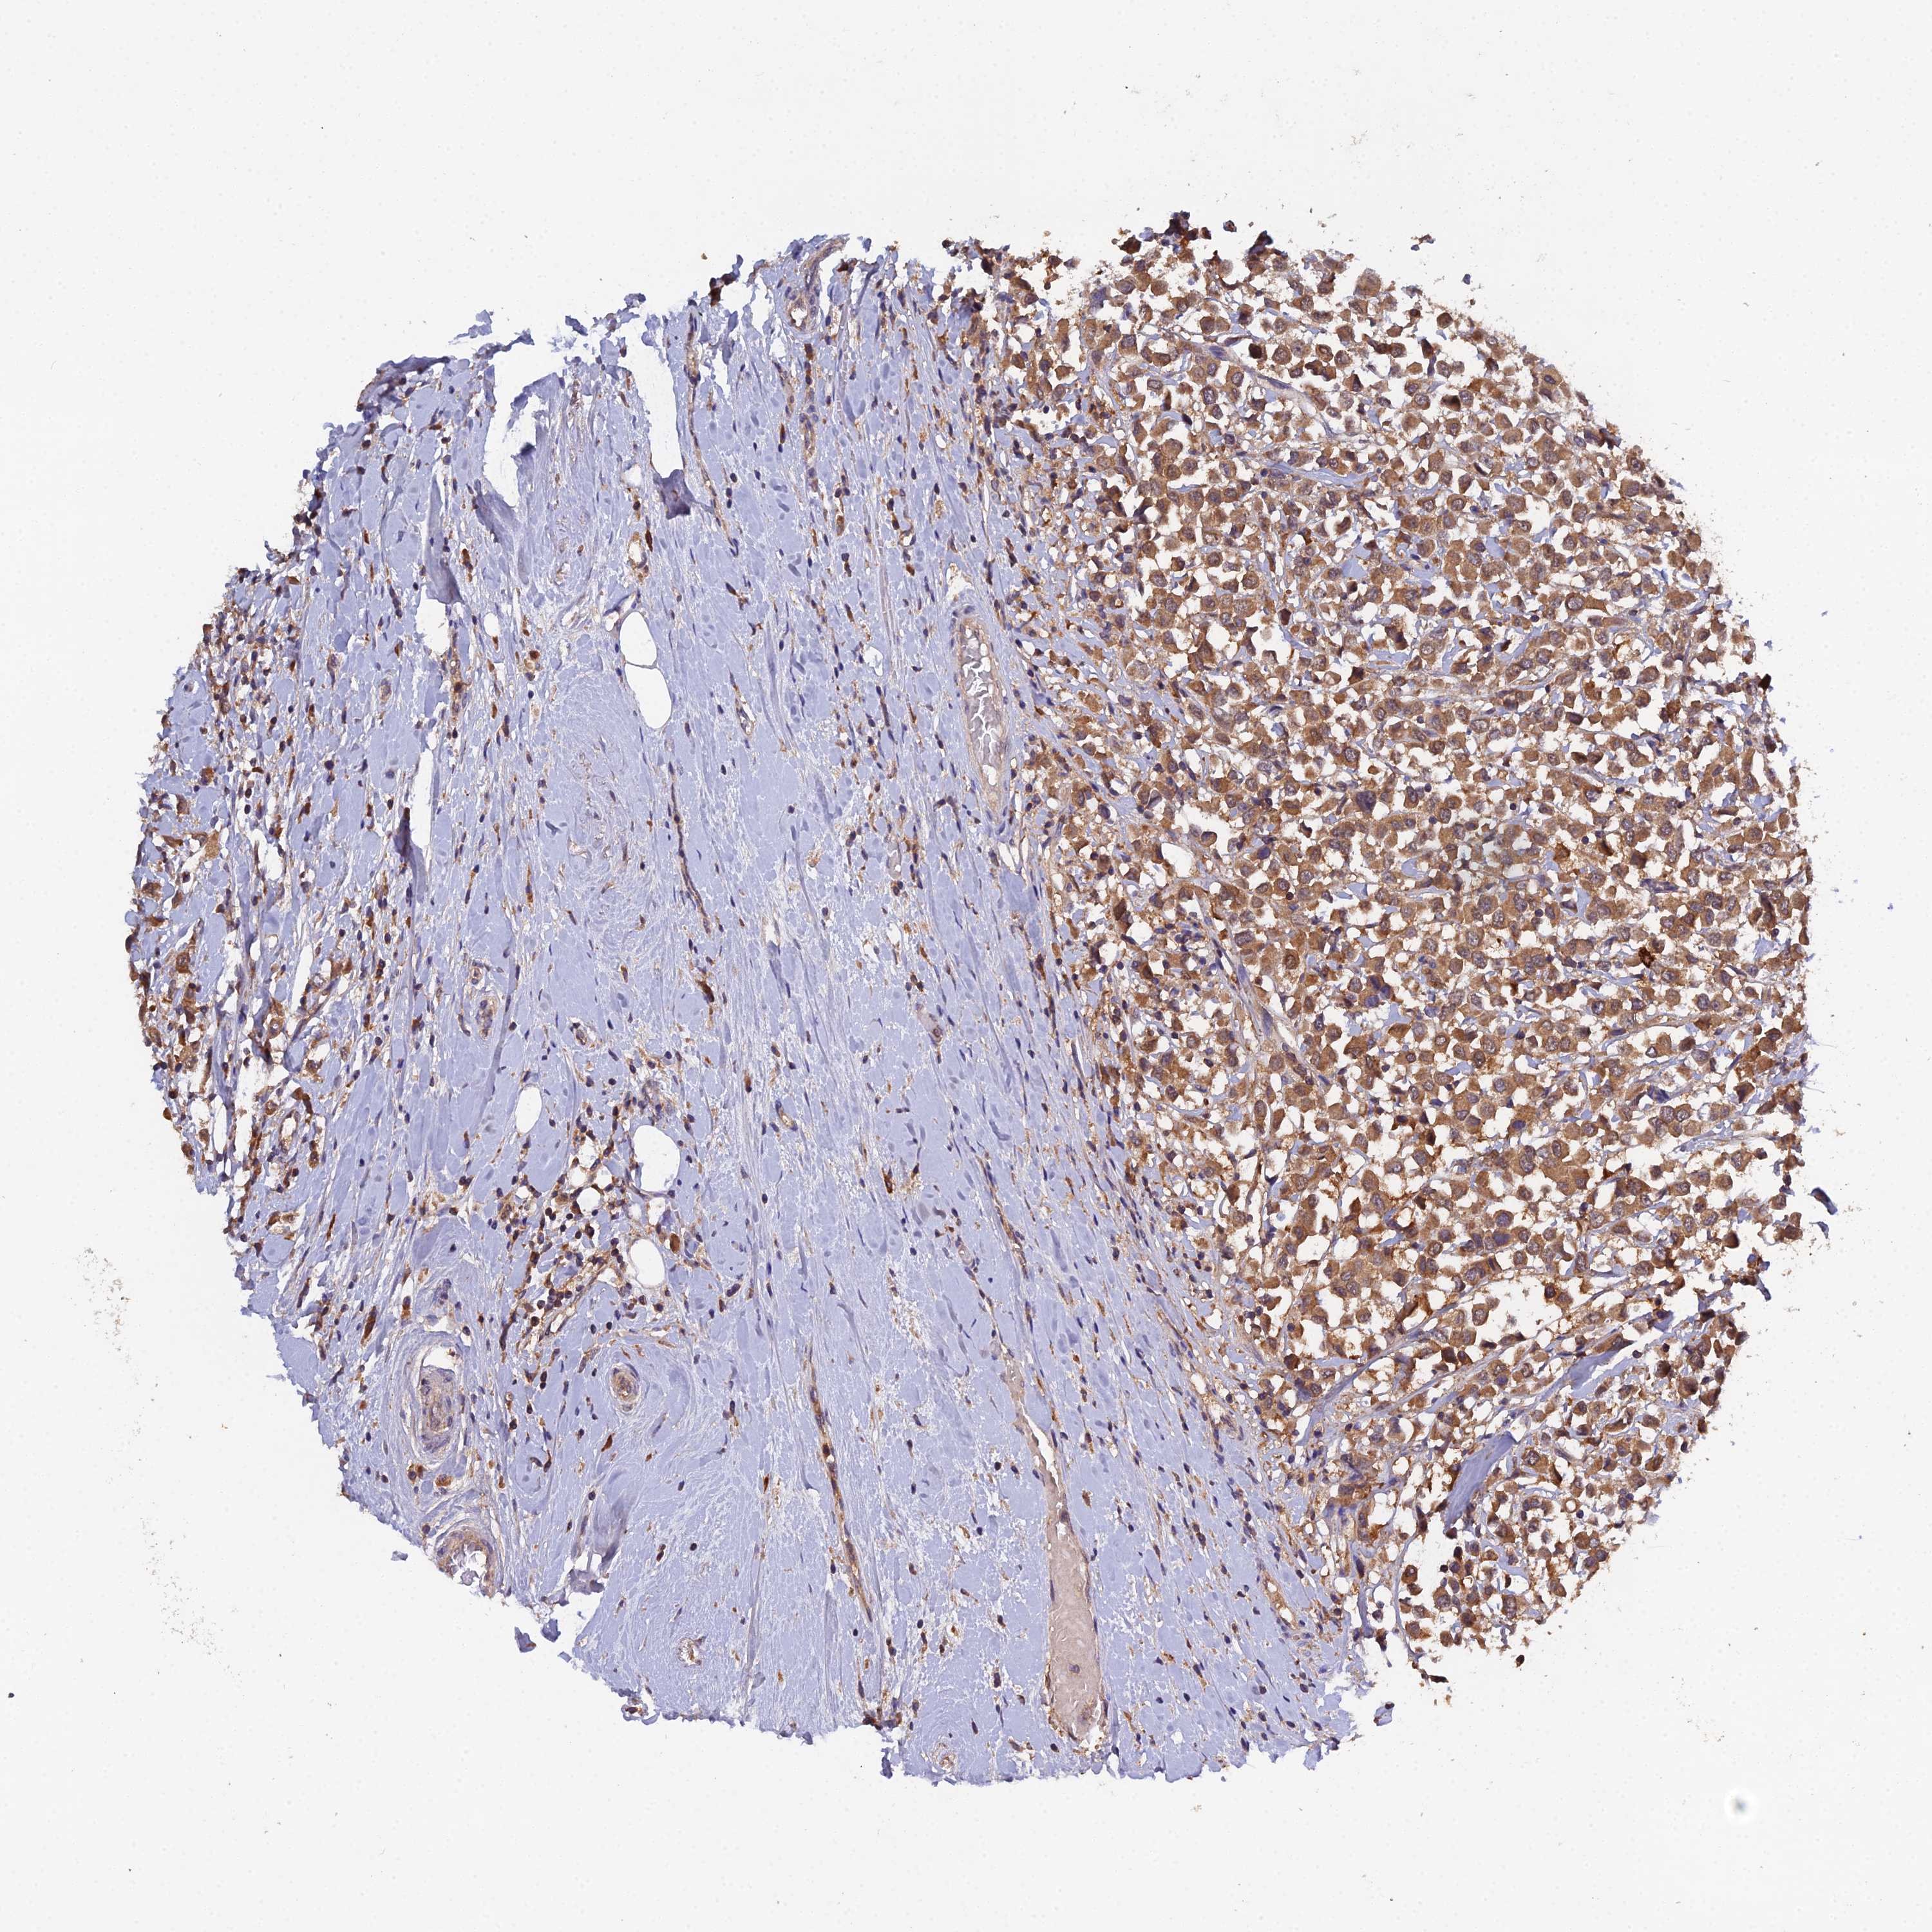

CANCER BREAST CANCER Show tissue menu

BRCA TCGA BRCA VALIDATION PROTEIN EXPRESSION